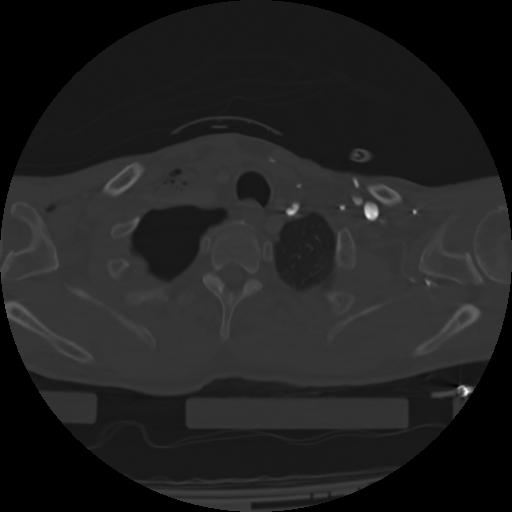

21 ANGIO,CE,Axial,3.0,ANGIO,,